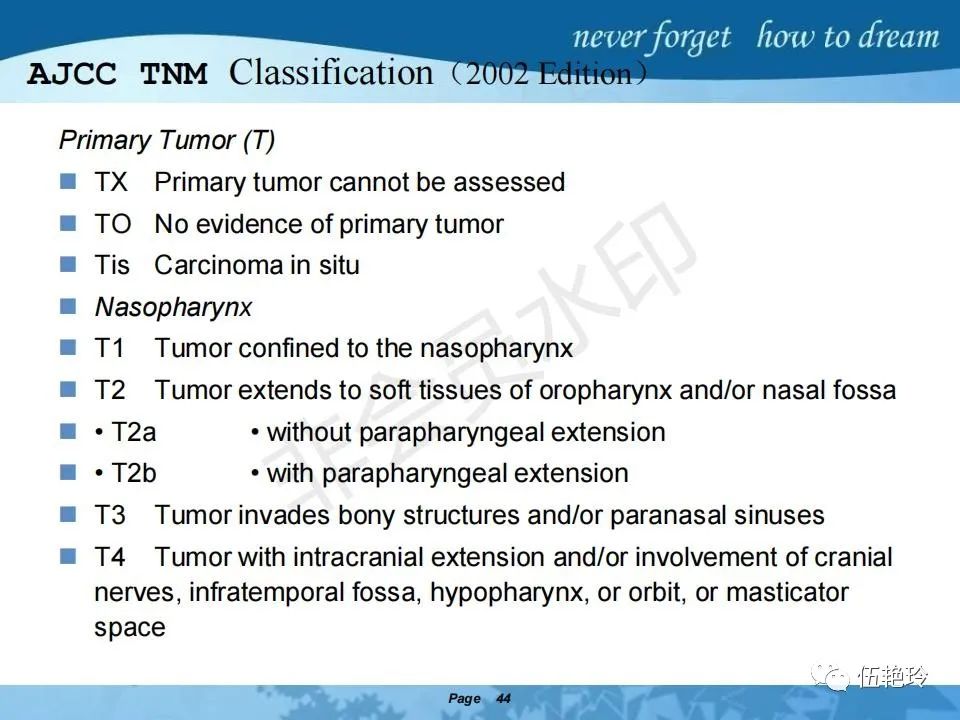

2.31 向上颅内:①鼻咽顶壁→破裂孔(岩尖、斜坡)→蝶窦、海绵窦;②鼻咽顶壁→蝶骨基底部→蝶窦、海绵窦;③鼻咽侧壁→茎突前间隙→蝶骨大翼(卵圆孔)→海绵窦;④鼻咽侧壁→茎突前间隙→翼腭窝→ 颞下窝;⑤鼻咽前壁→鼻腔→翼突、翼腭窝→眶下裂→眶尖→海绵窦;⑥鼻咽前壁→鼻腔→上颌窦、筛窦;

2.32向下颈椎:①鼻咽后壁→斜坡、颈椎→颅内;②鼻咽下壁→口咽(淋巴结多见)→下咽;③鼻咽下壁→口咽(淋巴结多见)→斜坡、颈椎。